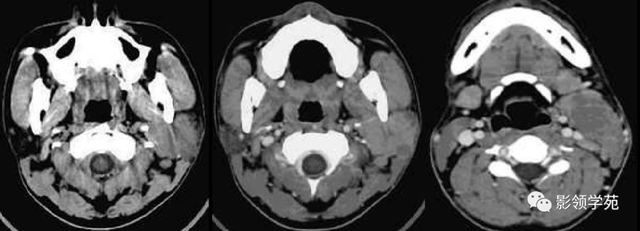

图6 a 、b 、c 囊腺癌 左侧腮腺弥漫性增大,密度增高,边缘无法确定,同侧颈部可见淋投合肿大坏死,胸锁乳突肌受侵占